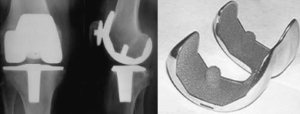

Όπως διαφαίνεται και από την ορολογία γίνεται μία “αρθροπλαστική” δηλαδή, πλαστική της άρθρωσης, δημιουργώντας μία νέα άρθρωση. Αυτό γίνεται, εκτέμνοντας τμήματα των κατεστραμένων αρθρικών επιφανειών και εφαρμόζοντας ισομεγέθη εμφυτεύματα που έχουν τη μορφή εκμαγείων στη θέση τους. Αυτά σταθεροποιούνται με μία ειδική “κόλλα” που ονομάζεται οστικό τσιμέντο. Αυτό έχει τη δυνατότητα να επιτυγχάνει άριστη συγκράτηση στο εμφύτευμα και το οστούν. Επειδή όμως μακροπρόθεσμα βρέθηκε ότι, το τσιμέντο μπορεί να προκαλέσει οστεόλυση και χαλάρωση του εμφυτεύματος, εφαρμόζεται και άλλη τεχνική σταθεροποίησης “χωρίς τσιμέντο”. Αυτό γίνεται μέσω της επαφής του εμφυτεύματος με το οστούν όπου, στην επιφάνεια επαφής δημιουργείται μία πορώδης επιφάνεια μέσα στην οποία διεισδύουν οστικά κύτταρα, επιτυγχάνοντας τη σταθεροποίηση οστού-εμφυτεύματος. Προϋπόθεση για τη τελευταία περίπτωση είναι η καλή ποιότητα του οστού.